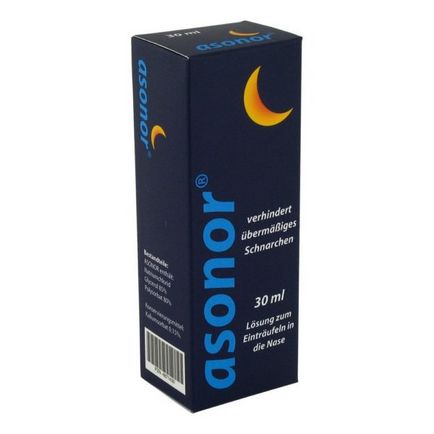

Lágyító és regeneráló hatású, hogy hidratálja a nyálkahártya, nazális hangok izmok. Alkalmazott lefekvés előtt, injektálunk mindkét orrlyukba részét alapok úgy, hogy a gyógyszer csöpögtettünk a torok.

Az alkalmazás után nem tud inni, fogmosás, vagy öblítse ki a száját. Eszközt, ami hatékony 7-8 óra. A gyógyszer nem szívódik fel a vérbe, nincs ellenjavallat. Asonornak is kiürül a cseppek formájában. Az ár 1500 rubel.